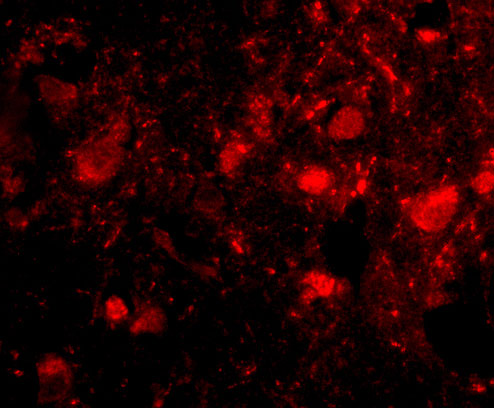

Immunofluorescence of slitrk3 in human brain tissue with slitrk3 antibody at 20 μg/mL. |